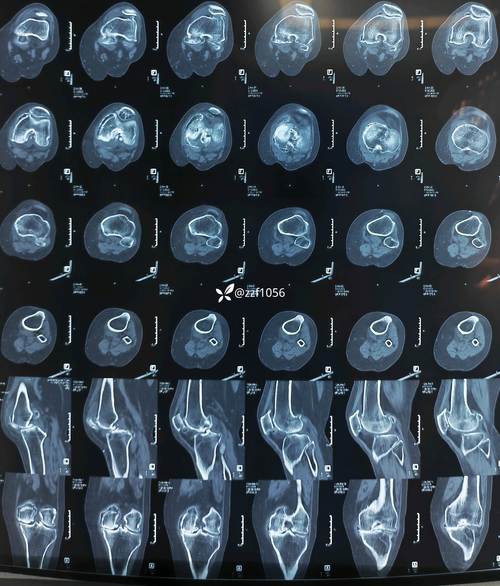

(图片来源网络,侵删)